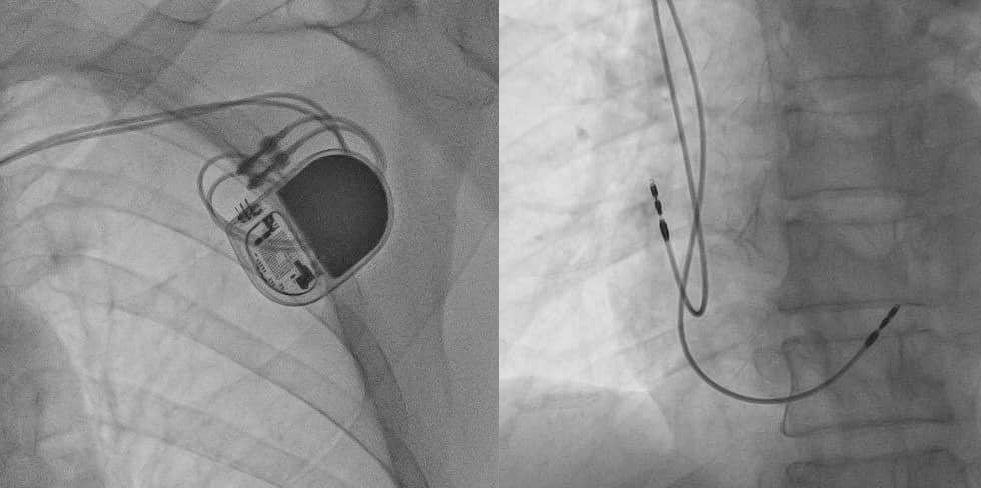

Với sự hỗ trợ của hệ thống máy DSA hiện đại , cho hình ảnh rõ nét, bệnh nhân đã được tiến hành đặt máy tạo nhịp hai buồng có đáp ứng tần số DDDR chỉ trong vòng 40 phút, áp dụng kỹ thuật tạo nhịp vách (là kỹ thuật tạo nhịp mới) giúp giảm nguy cơ rung nhĩ, hội máy tạo nhịp... Các thông số kiểm tra máy đều trong ngưỡng tối ưu. Bệnh nhân cải thiện nhịp tim và triệu chứng sớm ngay sau đặt máy.

Thủ thuật đặt máy tạo nhịp tim nên được tiến hành tại phòng Cathlab, đội ngũ chuyên nghiệp, giàu kinh nghiệm. Với hệ thống máy DSA hiện đại, mới được trang bị tại Bệnh viện Trường Đại học Y Dược Huế cho hình ảnh rõ nét, giảm liều chiếu tia và được trang bị nhiều phần mềm chuyên dụng hỗ trợ can thiệp, tạo nhịp giúp thủ thuật có thể tiến hành một cách nhanh chóng, hiệu quả và hạn chế tối đa biến chứng có thể gặp.